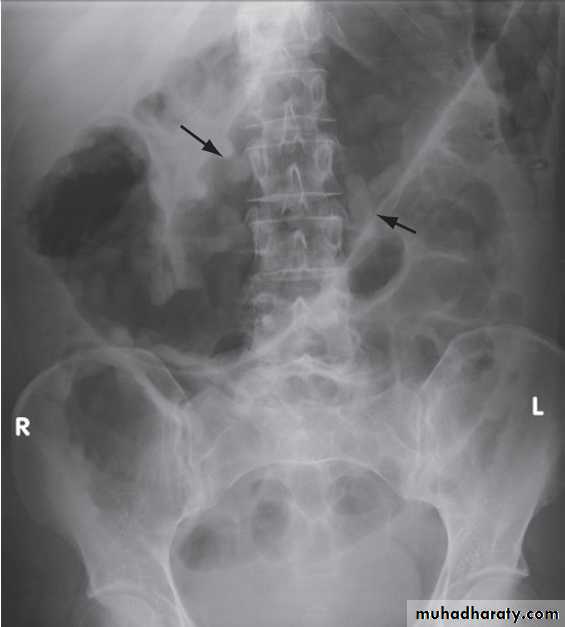

Colonic and anorectal motilityA plain abdominal X-ray taken on day 5 after ingestion of inert plastic pellets on days 1–3 gives an estimate of whole gut transit time. The test is useful in the evaluation of chronic constipation, when the position of any retained pellets can be observed, and helps to differentiate cases of slow transit from those due to obstructed defecation.